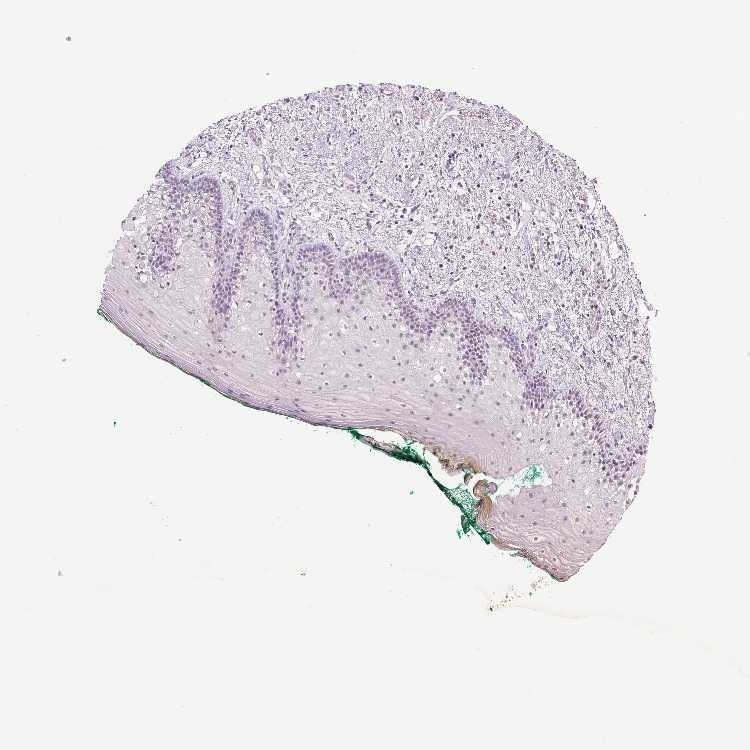

TISSUE PRIMARY DATA ORAL MUCOSA Show tissue menu

ORAL MUCOSA - Antibody stainingi

Antibody staining in the annotated cell types in the current human tissue is reported as not detected, low, medium, or high, based on conventional immunohistochemistry profiling in selected tissues. This score is based on the combination of the staining intensity and fraction of stained cells.

Each image is clickable and will lead to virtual microscopy that enables deeper exploration of all samples and also displays staining intensity scores, fraction scores and subcellular localization as well as patient and tissue information for each sample.

Squamous epithelial cells Not detectedNot detectedNot detectedNot detectedNot detectedNot detectedNot detected